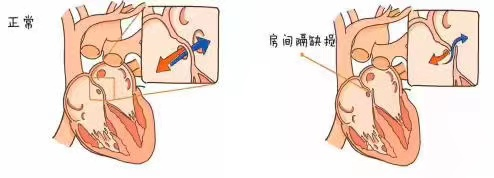

房间隔缺损是一种常见的先天性心脏病,是原始间隔在胚胎发育过程中出现的异常,致左、右心房之间遗留孔隙,儿童可无明显症状,青年期后可逐渐出现心悸、气促、乏力等活动耐量减退的表现,后期可出现心力衰竭、肺动脉高压等并发症,目前房间隔缺损的治疗手段主要是外科房间隔修补或介入封堵。

李勇主任表示,房间隔封堵术采用经股静脉穿刺的办法,将封堵伞片送至心房,修补位于左右心房间的缺损处,阻断心房水平的左向右分流,恢复正常的血液循环。相较于房间隔修补术,房间隔封堵术其优点是创口小,痛苦小,恢复快,避开了开胸、体外循环、心脏停跳等环节,手术全程由超声引导,实时了解心脏情况,判断手术效果,手术成功率高,现已广泛成熟应用于临床,房间隔缺损、室间隔缺损、动脉导管未闭等先天心脏疾病,均可以采取介入封堵方式治疗。

房间隔缺损封堵术示意图